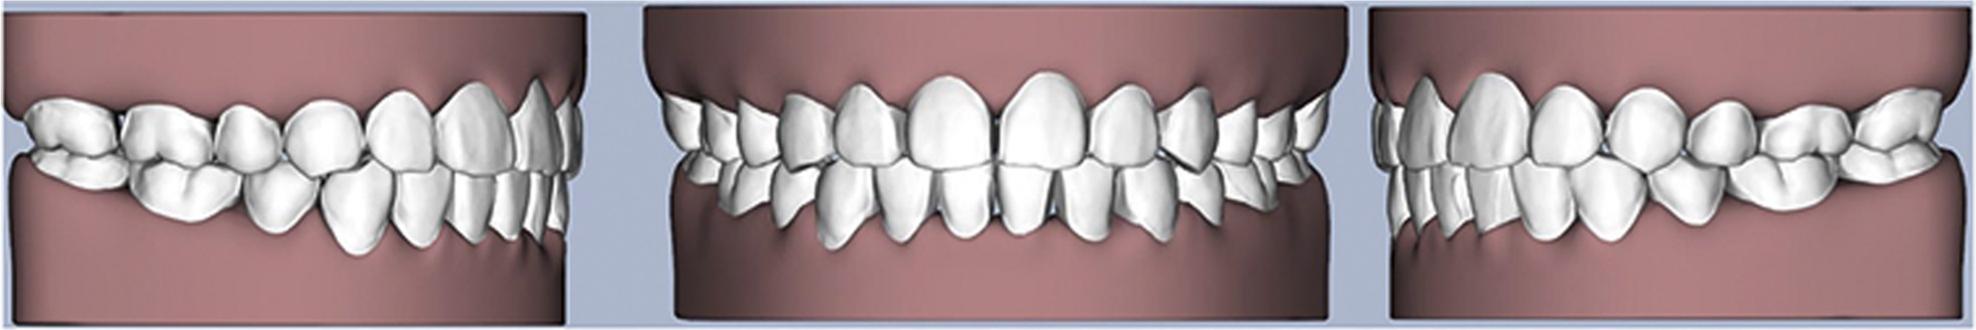

Figure 4.

Digital setup: simulation of the final occlusal relationship.